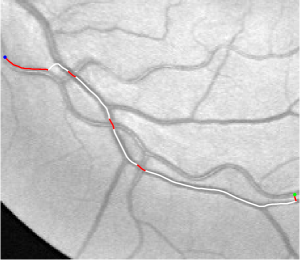

Compare to existing minimal path models. The Riemannian metrics used in [1, 4, 5] are based on the local pointwise information. The curvature-penalized metric [7, 6] and the proposed coherence-penalized metric are able to consider more constraints, i.e., the rigidity for [7, 6] and feature coherence for our metric. These constraints are beneficial to the respective geodesics to reduce the risk of short branches combination problem. Compared to the curvature-penalized metric, our method can be more flexible since the feature map can be produced dependently on the task. In retinal imaging, veins and arteries are distinguishable in terms of gray levels or vesselness values, satisfying the formulation of the proposed model. Especially for vessels with strong tortuosity, the curvature-penalized metric, which favours a smooth curve, fails to catch the expected vessels as shown in the left column of Fig. 2. From the right column of Fig. 2, one can see that our model can obtain a good result.